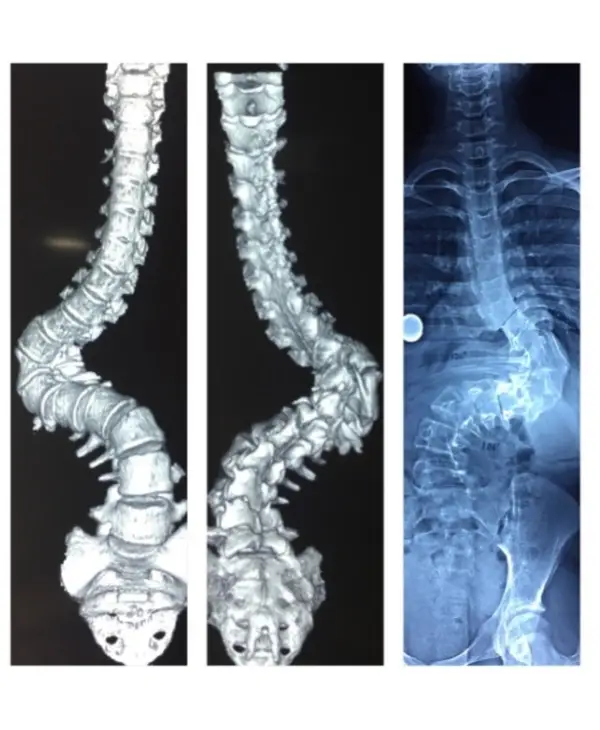

Diagnosis: Congenital scoliosis with hemivertebra and unsegmented bar

Treatment: Deformity correction with vertebral column resection(VCR) and cage reconstruction

Outcome: child returned to normal life with good self-esteem